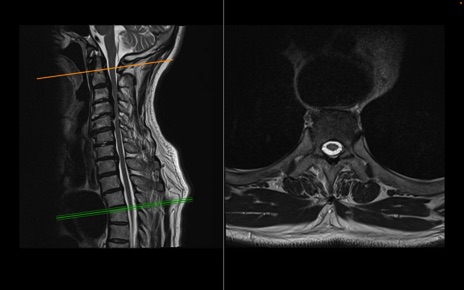

頚椎MRI

T2WI(横断像)

T2WI(矢状断像)